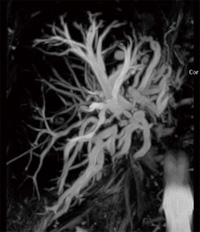

MRCPと同様に,非造影MRAの要望が年々高くなってきているが,MAGNETOMではsyngo NATIVEによって多くの部位での非造影MRAをも可能としている(図7)。

図7 syngo NATIVE